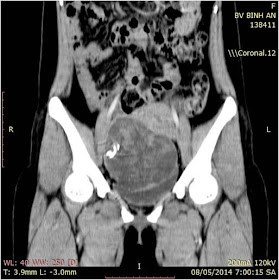

CASE 253: GOSSYPIBOMA (TEXTILOMA) POST CAESAREAN SECTION for a YEAR, Pham Hong Dong,M.D; Nguyen Duc Duy Linh,M.D; Phu Van Tuot,M.D; Nguyen Ngoc Xuan Giang,M.D., MEDIC Binh An Kien Giang Hospital

A 26 year-old female patient who had complained mild pain at her pubic region  presented lower abdominal pain a month prior. She  overwent a caesarean section a year ago for delivery her child.

Ultrasound findings:A cystic mass (about 83x46 mm) containing distinct internal hyperechoic wavy, striped structures.

CT Scan abdomen: A mass of 11 x 9 cm with thicken enhancing walls was seen in pelvis.

But diagnosis of gossypiboma was made and at laparotomy: a surgical sponge (18x22 cm) with adjacent inflammatory tissue and pus were removed successfully.